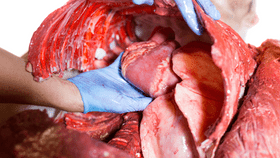

The model is crafted from silicone gel and fibers, with a similar texture to real-life skin, which can be slit open with a scalpel then seamlessly resealed. Inside the body, the model features lifelike simulations of the heart, lungs, and main vessels in the chest cavity. The researchers created the organs by conducting extensive CT scans to get a realistic and accurate replica of the organ’s structure.

Artificial blood can be pumped around the model to simulate the threat of blood-loss and the lungs can be ventilated to mimic the movement of a patient’s chest as they breathe.

My achy fakey heart. Nottingham Trent University